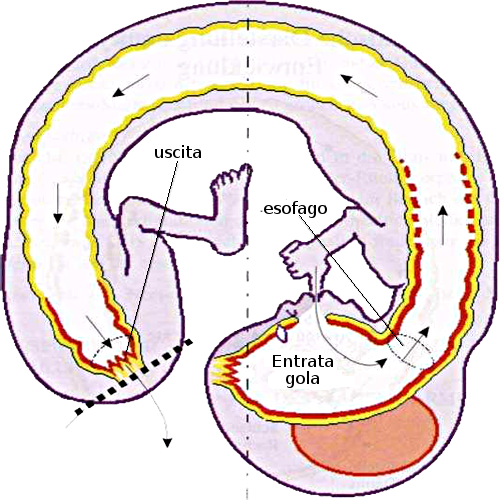

Sviluppo embrionario del tubo digerente

| Prima fase: forma arcaica ad anello | Seconda fase: forma embrionaria più tardiva |

L'anello arcaico era essenzialmente intestino. L'inizio del tratto intestinale (per l'entrata del boccone) era la parte destra, e la fine del tratto intestinale (per l'espulsione delle feci) era la parte sinistra della cavità. La forma ad anello dei nostri antichi predecessori si lacerò dando luogo alla formazione embrionaria attuale. La lacerazione è molto prossima alla parte sinistra della cavità arcaica orofaringo-anal, dopo questa lacerazione si creò una nuova parte finale dell'intestino (il

retto attuale), mentre la cavità, che rimase intatta, si convertì nella attuale bocca + faringe (inizio del tratto gastrointestinale). È importante capire la natura dei conflitti biologici arcaici nel contesto della nostra evoluzione, durante cosiddetto "periodo della faringe primitiva".

La forma ad anello arcaica dei nostri ancestri evolutivi si ruppe proprio sotto la faringe. La cavità faringea primitiva è divenuta l'attuale bocca, la cavità oro-faringea e l'ano (cavità oro faringo anale).

Questa rottura avvenne in un punto e nel momento in cui il nostro epitelio pavimentoso era già migrato 12 cm dalla faringe verso la parte rettale del tratto gastrointestinale adibita alla espulsione del boccone (retto). Questa è la ragione per la quale oggi troviamo mucosa epiteliale squamosa fino a 12 cm dall'ano verso il retto. Questo epitelio pavimentoso è innervato dalla corteccia Cerebralee e i relè della mucosa rettale si trovano precisamente al fianco dei relè delle derivazioni degli archi branchiali dell'antica faringe.

Nel cervello i centri di controllo della mucosa epiteliale squamosa del retto, della vagina, del collo uterino, della vescica urinaria compresi gli ureteri e la mucosa della pelvi renale (il cosiddetto epitelio transizionale), si trovano disposti in maniera ordinata, nei pressi dei siti Cerebralei dei derivati degli archi faringei della antica faringe primitiva.